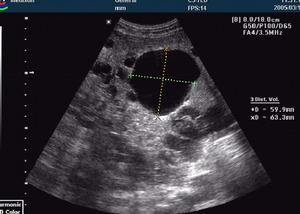

輔助檢查